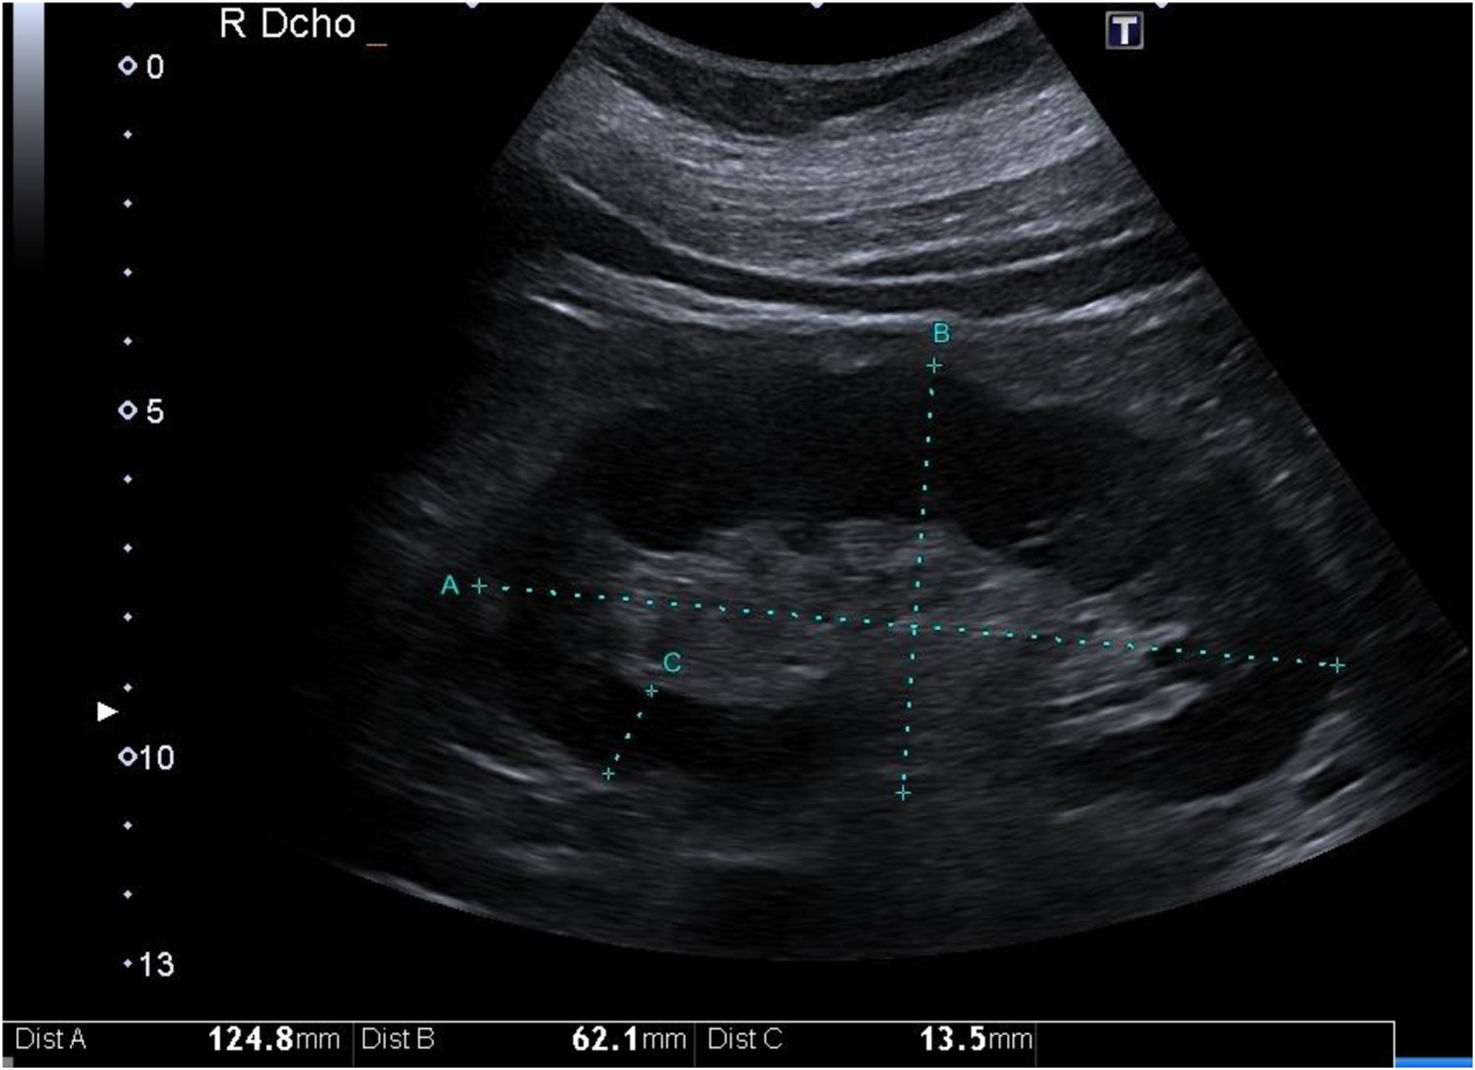

Grosor parenquimatoso, grosor cortical y ancho renalExiste correlación del grosor parenquimatoso con el grado de ERC mejorando estadísticamente esta asociación si se corrige por altura corporal1. Se ha asociado inversamente con el grado de atrofia tubular. Sin embargo, no es así con el espesor cortical11 (fig. 1).

El espesor parenquimatoso corregido fue el único parámetro de modo B (excluido la ecogenicidad parenquimatosa) que se redujo de forma progresiva conforme disminuía el FGe. Este parámetro demostró tener mayor especificidad según la curva ROC para distinguir un FGe inferior a 60mL/min comparado con las curvas ROC de la longitud, cortical y ancho renal. Sin embargo, presentó un área bajo la curva (AUC) inferior en comparación con la ecogenicidad del parénquima renal1,12.

El parámetro del grosor de la corteza renal es poco utilizado por los investigadores por la dificultad de medición en pacientes con mala diferenciación coticomedular, hallazgo que se observa más frecuentemente en paciente con ERC avanzada. Al presentar una interfaz difícil de identificar, la reproductibilidad es baja, por este motivo pocos estudios lo utilizan y esto se traduce en que no haya datos consistentes acerca de la asociación de grosor de la corteza renal y deterioro de función renal. Asimismo, Beland et al.13 demostraron que el grosor de la cortical estaba estrechamente correlacionado con el FGe (fig. 2).